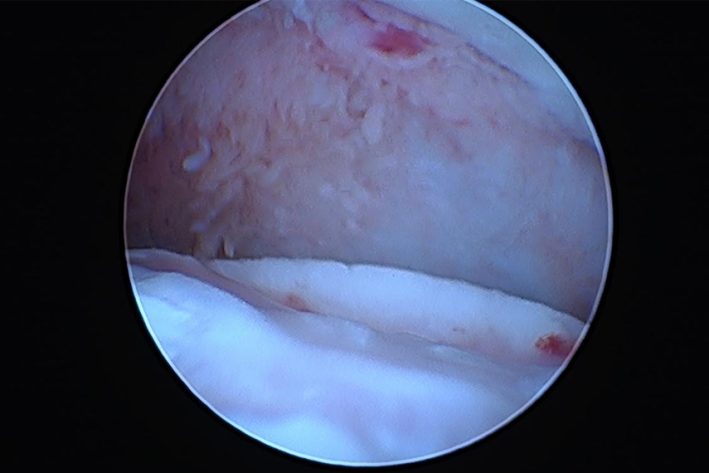

Die Schuppe wurde entfernt. OCD Bett in Abheilung